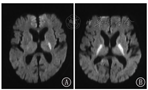

3.4 局灶性病变/脑梗死有新生儿癫痫,但Apgar评分相对正常和需要复苏的婴儿,通常存在局灶性缺血性或出血性病变。局灶性缺血通常以大脑中动脉梗死的形式出现,最常累及左半球(图10)。一般来说,在第1周结束时进行扫描能更好地判断病变范围。在少数婴儿中,早期常规MRI图像的异常可能非常细微。相比之下,同期的DWI将能够突出扫描的梗死区域[11]。DWI的异常在第1周结束时变得不明显,此时常规T1WI和T2WI的异常信号却十分明显。

图10

大脑中动脉梗死新生儿 A:左侧大脑中动脉区梗死;B:头颅磁共振血管造影:左侧大脑中动脉主干梗阻

Figure 10

Newborn with middle cerebral artery infarction A:left middle cerebral artery territory infarction;B:left middle cerebral artery main branch obstruction (arrow showed) is evident in magnetic resonance angiography image